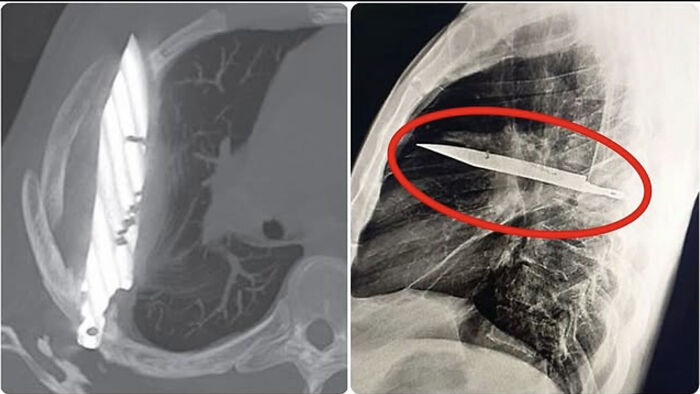

A 44-Year-Old Man Arrived At The Hospital With A Strange Chest Wound. During The Examination, The Doctors Discovered That A Knife Blade Had Been Lodged In His Chest For Eight Years—without His Knowledge At All

It turns out that he was st*bbed years ago, and the wound was stitched without a deep examination. Since then, he had lived normally with no special symptoms—until the wound began to bleed, and the hidden blade was revealed in an X-ray.

The blade was surgically removed, the patient recovered, and he was discharged within a few days.